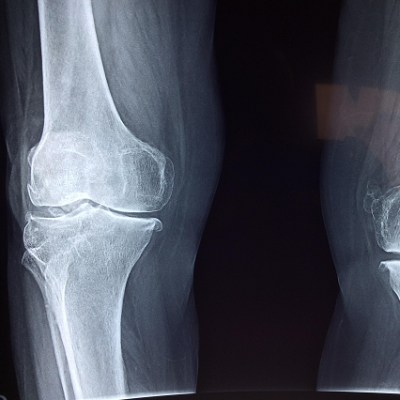

With an ageing population, sport injuries and obesity among the causes, the rate of joint replacement surgery is increasing at a rapid rate.  Currently more than 85,000 hip and knee replacements are undertaken each year in Australia. The outcomes of joint replacement are variable.